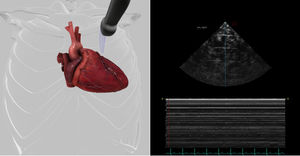

... Los módulos de patología de HeartWorks para la TTE y la TEE han sido creados para facilitar la evaluación ecocardiográfica de pacientes con alteraciones estructurales y hemodinámicas. Este módulo incluye ...

Inventive Medical Limited